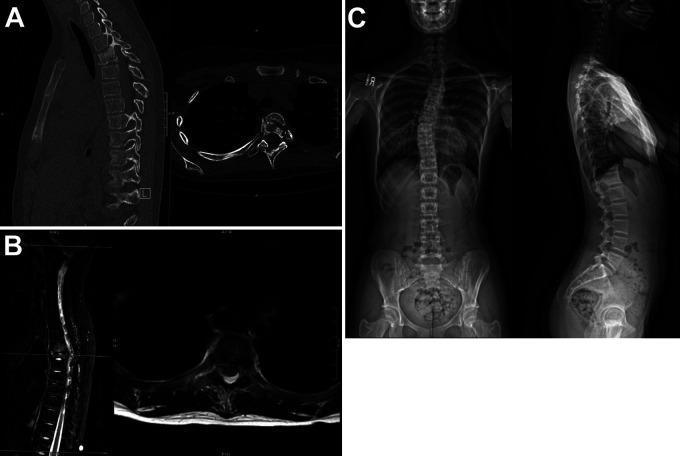

Fifty-six pediatric patients with clinical and radiographic evidence of CRMO were identified and clinical, radiographic, laboratory, and histopathological data were reviewed. All were evaluated via Jansson and Bristol CRMO diagnostic criteria. Ten had radiographic evidence of vertebral involvement (17.9%). Nine of these had multifocal disease. Five patients had multiple vertebrae affected. Six patients were evaluated for possible surgical intervention and one required intervention due to vertebra plana leading to a progressive kyphotic deformity and significant spinal canal stenosis.

确定了56例有CRMO临床和影像学证据的儿科患者,并回顾了其临床、影像学、实验室和组织病理学数据。所有患者均通过扬松和布里斯托尔CRMO诊断标准进行评估。其中10例有椎体受累的影像学证据(17.9%)。其中9例有多灶性病变。5例患者有多个椎体受累。6例患者接受了可能的手术干预评估,1例因椎体扁平导致进行性后凸畸形和严重椎管狭窄而需要干预。